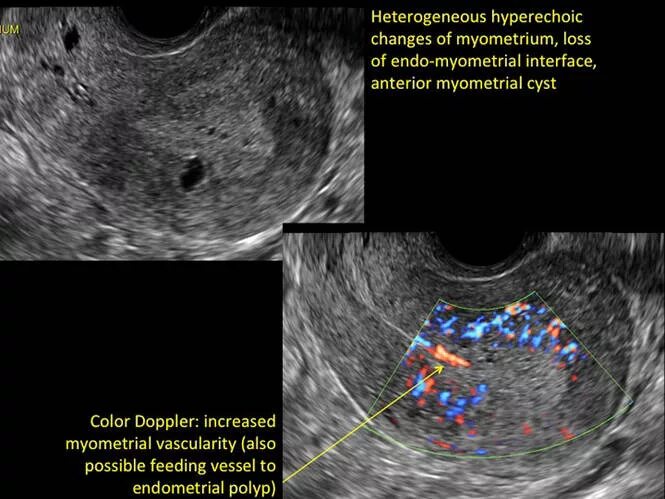

Эндометрий 9 мм